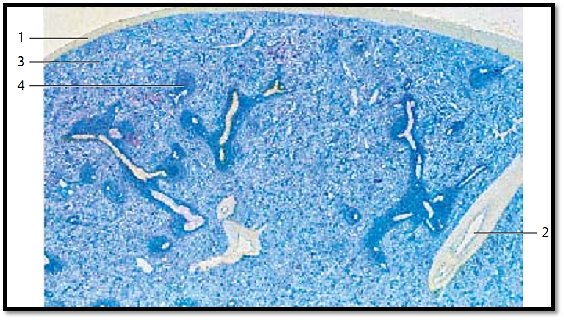

The spleen is the largest lymphatic organ in the human body. It is enveloped by a collagen fiber capsule 1 , which has a covering of peritoneal epithelium (top of the figure). Irregularly arrange d connective tissue cords traverse the organ, starting at the outer capsule. They are named splenic trabeculae 2 (almost unstained in this preparation) and contain the trabecular blood vessels. Richly vascularized reticular connective tissue occupies the space between splenic capsule and trabeculae. The abundance of blood explains the name re d spleen pulp 3 for the flexible reticular web. The pulp contains splenic follicles 4 (stained darker blue), which in their entirety represent the white pulp . This white pulp forms a reticular tissue with many lymphocytes, which surrounds the vessels like a sheath. Many of these vessels are cut longitudinally in this preparation.

1 Capsule

2 Spleen trabeculae with trabecular vein

3 Red splenic pulp

4 Splenic nodule with central artery

Stain: alum hematoxylin; magnification: × 4